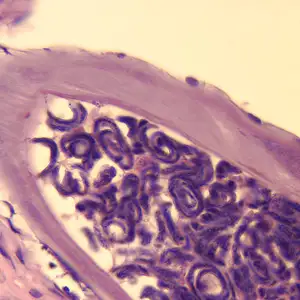

当感染性幼虫进入人体皮肤后,它们会在数月内发育成熟。雄虫相对较小,体长约2至4厘米,细如发丝;而雌虫则可达30至50厘米长,直径约0.3至0.4毫米,是名副其实的"巨虫"。成虫并不四处游荡,它们将自己蜷曲成团,深埋在皮下结缔组织中,形成特征性的纤维结节——医学上称为"盘尾丝虫结节"或"蟠尾蚴瘤"。

这些结节通常出现在骨性突起部位附近,如髋部、肋骨、肩胛骨和头颅。结节大小不一,从豌豆大小到高尔夫球大小不等,触感坚硬,通常无痛。一个感染者体内可能只有一两个结节,也可能多达数十个。在严重感染的病例中,结节几乎可以出现在身体的任何部位,包括头部和眼部周围。

然而,真正造成伤害的不是成虫,而是它们生产的微丝蚴。这些微小的幼虫体长仅约300微米,直径不到1微米,必须在显微镜下才能观察到。它们没有围鞘,身体纤细,尾部逐渐变尖。一旦离开母体,微丝蚴便开始在宿主的皮肤和皮下组织中四处迁移。